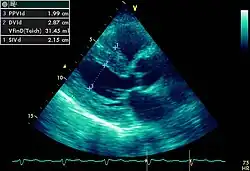

Hipertrofia ventricular esquerda é o espessamento da parede do ventrículo esquerdo. Apesar de encontrarmos no electrocardiograma sinais eléctricos de hipertrofia o seu estudo é feito pormenorizadamente em ecocardiografia.[1]